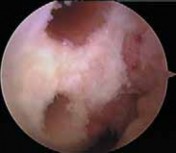

8. Radiographs of the knee should be performed following an acute injury to assess for a fracture. An avulsion of the tibial insertion of the PCL may be identified on a lateral radiograph (

FIG 1A

).

FIG 1 • A. Avulsion fracture of the tibial insertion of the posterior cruciate ligament (PCL). B. Posterior subluxation of the

tibia in a case of chonic PCL deficiency.

1. In the chronic setting, radiographs may identify posterior tibial subluxation (

FIG 1B

) or medial and patellofemoral compartmental arthrosis.